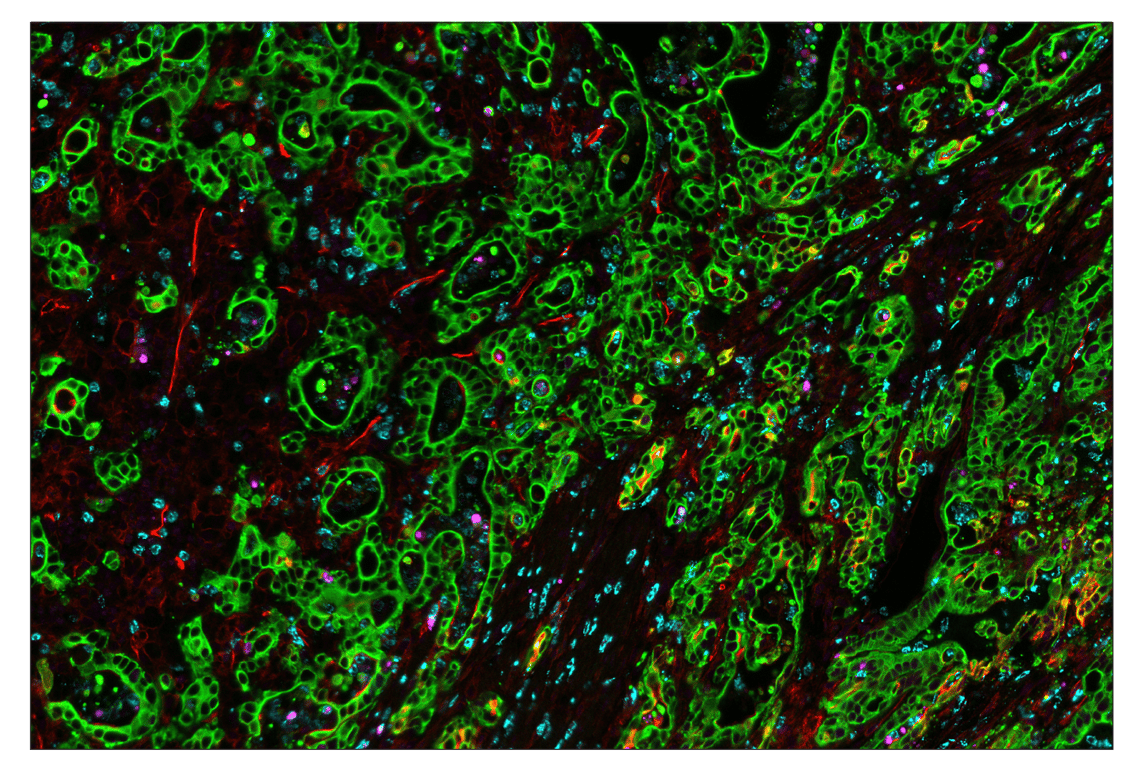

SignalStar multiplex immunohistochemistry (mIHC) is a tool that employs antibodies, oligonucleotides (oligos), and fluorophores to interrogate the cellular presence, location, function, and biomarker co-expression patterns. SignalStar technology enables the detection of multiple phenotypic and functional targets while maintaining spatial context and tissue architecture. These insights are essential for understanding how cells organize and interact to influence the tissue microenvironment and drive disease progression and response to therapy.

The power of the SignalStar system lies in the design of the SignalStar antibodies. These antibodies have been rigorously validated for use in formalin-fixed, paraffin-embedded (FFPE) tissues, and subsequently conjugated to unique oligo tags using site-specific conjugation and thorough purification methodologies. Using a highly specific network of complementary oligos and fluorophores, scientists can amplify the signal for 3-8 targets, even if they are in low abundance.

Figure 1. All antibodies in your plex size of choice (3-8 maximum unique oligo-conjugated antibodies) are added in cocktail in one primary incubation step. Complementary oligos with fluorescent dyes (channels: 488, 594, 647, and 750) amplify the signal of up to 4 oligo-conjugated antibodies in the first round of imaging by building oligo-fluorophore constructs attached to the antibody. If the plex size is greater than 4, the first round of oligos and fluorophores are gently removed, and a second round of amplification is performed to visualize up to 4 additional oligo-conjugated antibodies; the complementary oligo system and the use of the fluorophore removal process enables a second round of antibodies to be amplified from the same substrate, without cross-reactivity. The 2 images are then aligned and fused computationally with either proprietary or open-source software to generate an image consisting of up to 8 targets.

SignalStar™ Multiplex Immunohistochemistry (mIHC) is a technology that employs antibodies, oligonucleotides (oligos), and fluorophores to interrogate cellular presence, location, function, and biomarker co-expression patterns. SignalStar technology enables the detection of multiple phenotypic and functional targets while maintaining spatial context and tissue architecture. These insights are essential for understanding how cells organize and interact to influence the tissue microenvironment and drive disease progression and response to therapy.

The power of the SignalStar system lies in the design of the SignalStar antibodies. These antibodies have been rigorously validated for use in formalin-fixed, paraffin-embedded (FFPE) tissues, and subsequently conjugated to unique oligo tags using site-specific conjugation and thorough purification methodologies. Using a highly specific network of complementary oligos and fluorophores, scientists can amplify the signal for 3-8 targets, even if they are in low abundance.

Figure 1. All antibodies in your plex size of choice (3-8 maximum unique oligo-conjugated antibodies) are added in cocktail in one primary incubation step. Complementary oligos with fluorescent dyes (channels: 488, 594, 647, and 750) amplify the signal of up to 4 oligo-conjugated antibodies in the first round of imaging by building oligo-fluorophore constructs attached to the antibody. If the plex size is greater than 4, the first round of oligos and fluorophores are gently removed, and a second round of amplification is performed to visualize up to 4 additional oligo-conjugated antibodies; the complementary oligo system and the use of the fluorophore removal process enables a second round of antibodies to be amplified from the same substrate, without cross-reactivity. The 2 images are then aligned and fused computationally with either proprietary or open-source software to generate an image consisting of up to 8 targets.